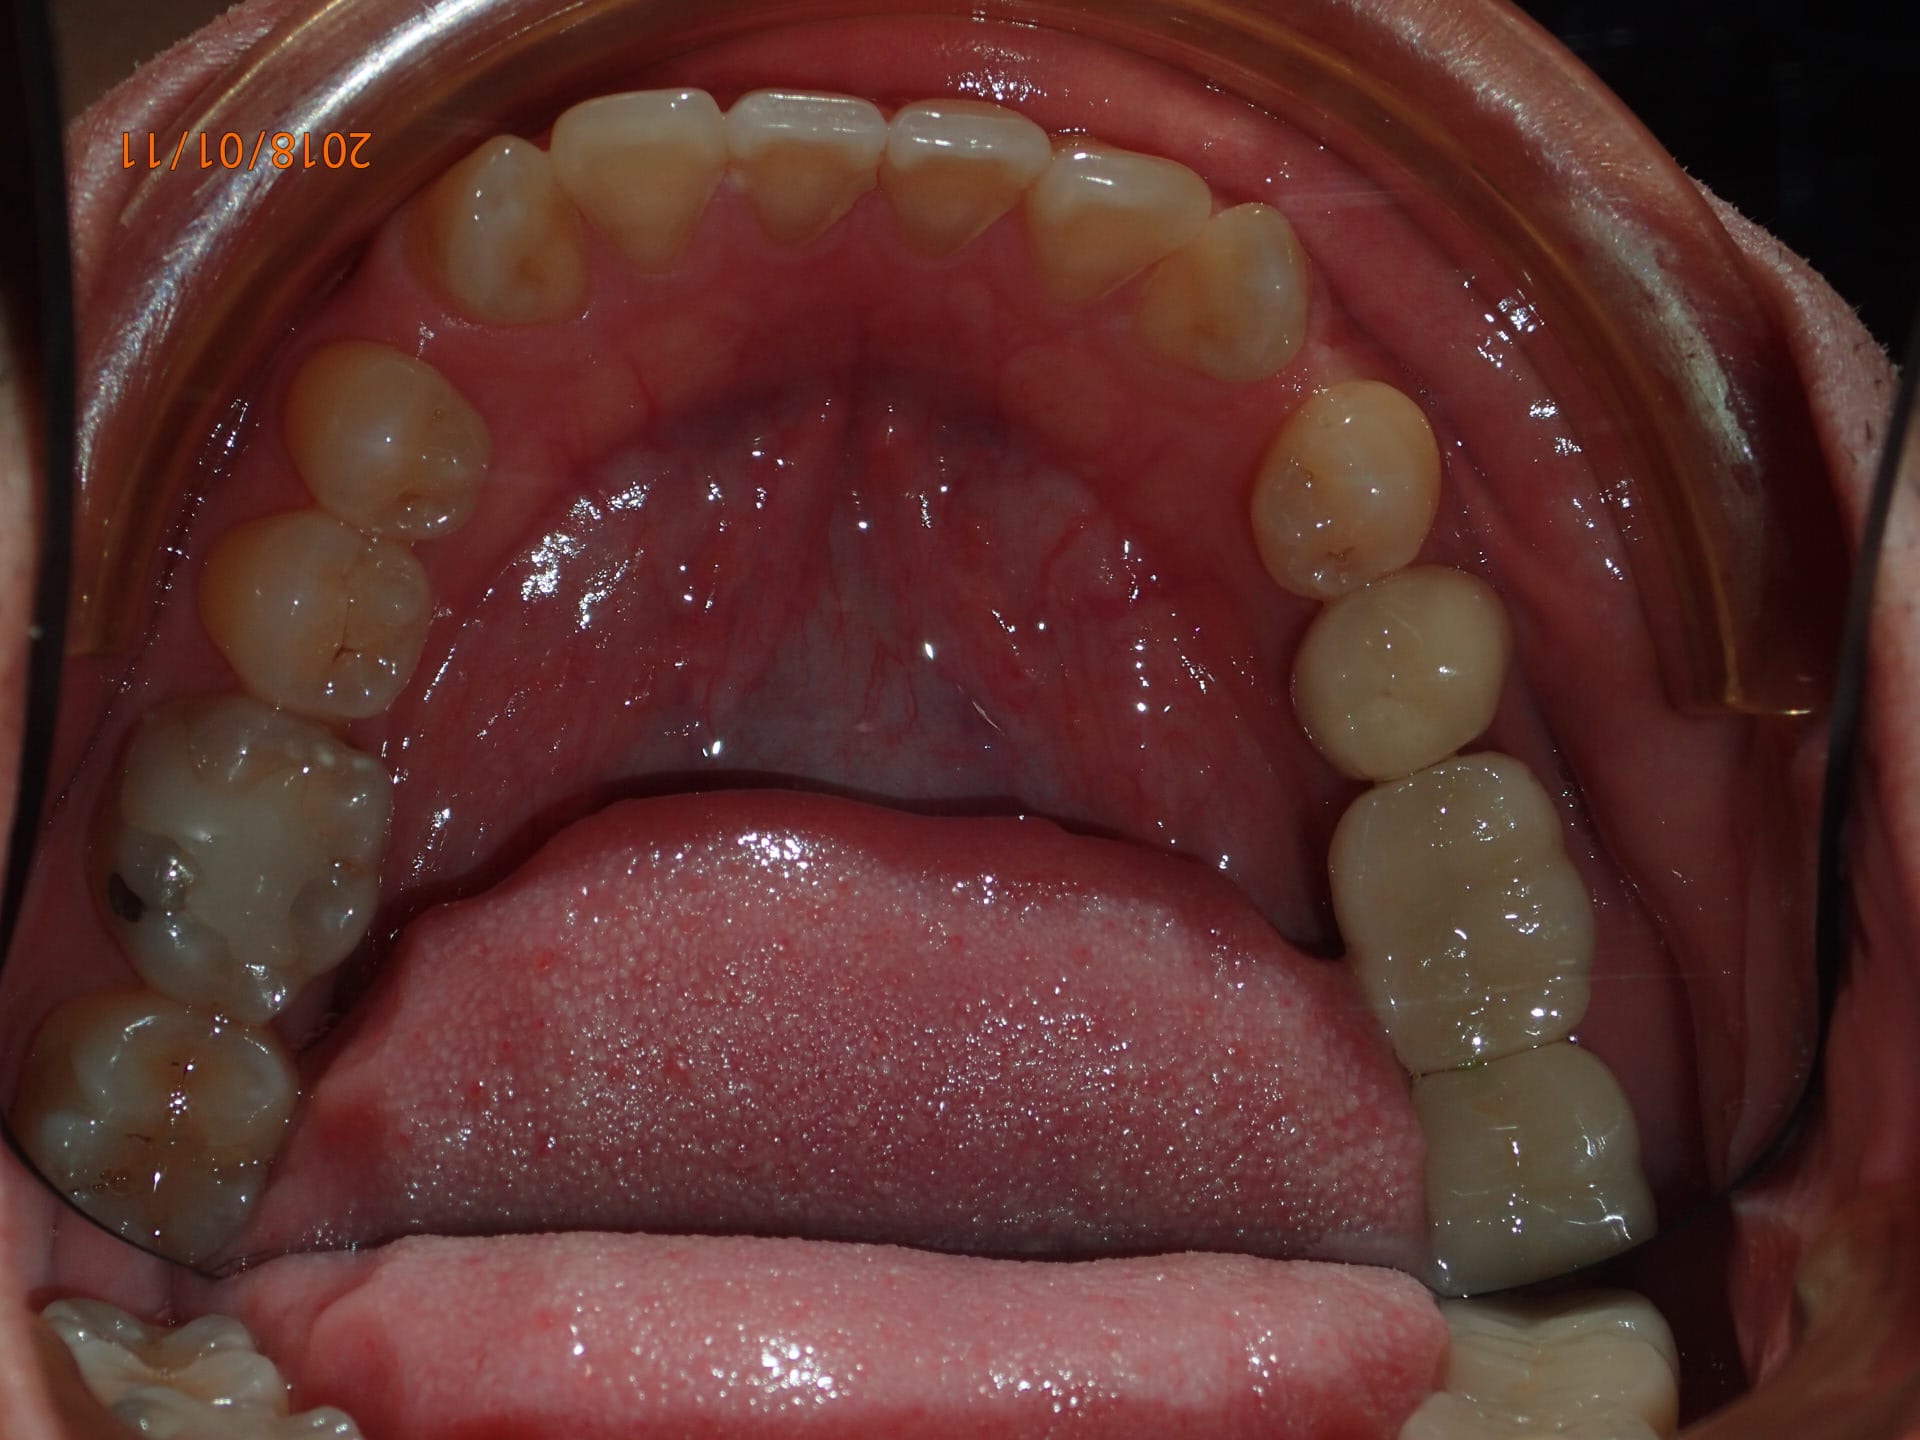

Et mon très probable nouveau cas 2D.

Patient accompagnant un autre patient, en discutant je remarque l'encombrement antérieur mandibulaire et mentionne l'ortho pour lui.

' je suis trop vieux pour des bagues " , je lui explique que le lingual existe, pano, examen.

Il est très tenté par le lingual mais n'est pas sure de vouloir commencer la semaine prochaine, no soucie je prend une simple empreinte alginate et met un rendez vous entre deux patients la semaine d'après. Si il souhaite faire le traitement il doit me confirmer 48 heure avant.

Collage indirect sur les modéle en plâtre en 20 minutes, 5 minutes pour le trays de transfert, 1 minute pour plier le premier fil sur le modéle en plâtre.

Côut du matos endessous de 200$

Aucun autre système lingual n'offre cette réactivité :-)